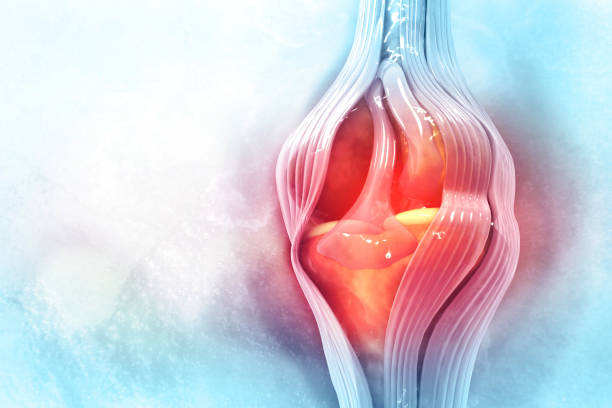

연골손상에 의한 무릎 통증

연골은 뼈와 뼈 사이의 마찰을 줄이고 충격을 흡수하는 기능을 합니다. 무릎의 연골손상은 무릎 통증의 일반적인 원인 중 하나입니다. 연골손상은 다양한 원인으로 발생할 수 있으며, 가장 흔한 원인은 무릎 관절 내의 충격이나 비대칭적인 압력에 의해 발생하는 외상입니다. 연골손상은 통증, 부종, 불안정성, 감각 손실 등의 증상을 일으킬 수 있습니다. 치료는 무릎 관절을 안정시키는 운동, 연골 재생을 촉진하는 약물 치료, 수술 등이 있습니다.